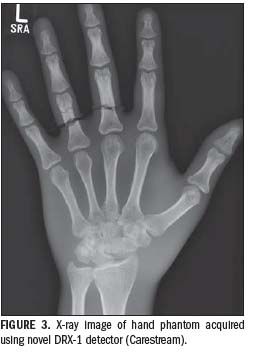

Another DR system of the future, Carestream’s DRX-1, is being tested now at our hospital (Figure 3). This digital radiographic image-capture system is used in conjunction with a conventional (analog) x-ray generation system from an original equipment manufacturer to produce digital projection radiographs of the human body. Data acquired by the detector are transmitted to the system console for storage, processing, display, and distribution to the healthcare facility network.

At the heart of the DRX-1 system is a thin flat-panel x-ray detector housed in a special cassette. It conforms dimensionally to the ISO 4090 standard and can be installed in an existing bucky as a direct and interchangeable replacement for existing CR or screen-film cassettes. The detector contains a full-field TFT readout array and integrated electronics for data storage and transmission. These can be powered by the DRX-1 detector’s internal rechargeable battery or through an electrical tether interface/cable connected to an external power supply.